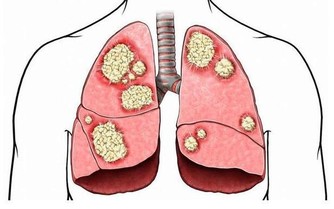

據美國紐約一家專門從事癌癥研究的權威機構透露,中國和日本婦女乳腺癌的發病率比西方低得多,這是為什麼呢?

科學家在比較了世界各國的三餐食譜後得出結論:是由於中國和日本婦女多吃大白菜的緣故。

調查資料表明,每10萬名婦女中,每年乳腺癌的發病率為:中國9人,日本21人,北歐84人,美國91人。

實驗證明,大白菜所含有的許多物質、具有防癌抗癌的作用,因此在美國國立癌癥研究所、發表的防癌食品排行榜中、將白菜排在僅次於大蒜的後面,名列第二。。

維生素C也叫抗壞血酸,能夠阻止致癌物質亞硝胺的生成,同時能抑製癌細胞的增殖。

其次,大白菜含有一種叫做吲哚-3-甲醇的化合物,其含量約佔大白菜重量的0.01%,它能促進人體產生一種重要的酶,這種酶能夠有效抑製癌細胞的生長和分裂。

能夠防止致癌物亞硝銨合成的微量元素鉬、大量存在於大白菜中,能阻斷亞硝胺等致癌物質在人體內的生成,所以能防止癌癥的發生。

如果人體缺硒,就好象失去了一道抵抗癌癥的堅固防線。硒也是人體一種重要的過氧化酶的組成部分,這種酶不僅可以防止不飽和脂肪酸的氧化,還能夠抑製可能成為致癌過氧化物和遊離基的形成。

科學家們認為,硒通過吞噬細胞的功能、能夠影響癌細胞的能量代謝、和幹擾癌細胞的蛋白合成,從而抑製癌癥,還能夠影響化學致癌物的代謝,使它們失去致癌的活性。